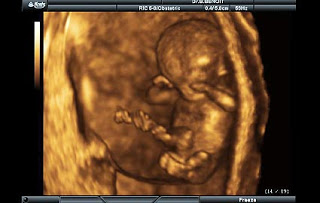

13. gebelik haftasında bebeğin boyu yaklaşık olarak 7 cm, ağırlığı 20 gram kadardır.

Bebeğin gözleri daha önce birbirinden uzakken bu haftada birbirine yaklaşmaya başlar,

kulaklar normal yerlerine doğru ilerler ve bebeğin yüzü normal insan yüzüne benzemeye

başlar. Bebeğin ses telleri oluşmaya başlar. Bu haftada bebeğe yakından bakılabilse,

cinsiyeti dış genital organlarına bakarak söylenebilecek kadar gelişmiştir. Bu haftalarda

ancak çok gelişmiş ultrason cihazları ile cinsiyeti tahmin edilebilir, daha net görülebilmesi

için bir kaç hafta daha büyümesi gerekecektir. Bu haftada bebeğin karaciğerinden safra

sıvısı salgılanabilir, pankreas bezinden insülin üretimi başlamıştır. Bebeğin damaklarının

altında 20 adet dişi oluşmuştur. Bebek içerisinde bulunduğu amnion sıvısını yutar ve

tekrar idrar olarak çıkartır, idrar da amnion sıvısına karışır. (linkten alıntı)